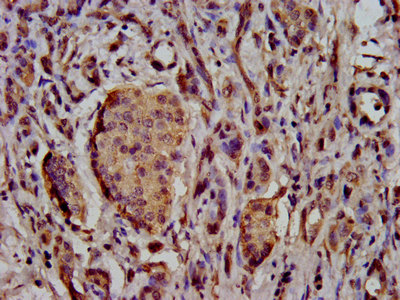

IHC image of CSB-PA883417LA01HU diluted at 1:500 and staining in paraffin-embedded human cervical cancer performed on a Leica BondTM system. After dewaxing and hydration, antigen retrieval was mediated by high pressure in a citrate buffer (pH 6.0). Section was blocked with 10% normal goat serum 30min at RT. Then primary antibody (1% BSA) was incubated at 4°C overnight. The primary is detected by a biotinylated secondary antibody and visualized using an HRP conjugated SP system.

IHC image of CSB-PA883417LA01HU diluted at 1:500 and staining in paraffin-embedded human pancreatic cancer performed on a Leica BondTM system. After dewaxing and hydration, antigen retrieval was mediated by high pressure in a citrate buffer (pH 6.0). Section was blocked with 10% normal goat serum 30min at RT. Then primary antibody (1% BSA) was incubated at 4°C overnight. The primary is detected by a biotinylated secondary antibody and visualized using an HRP conjugated SP system.